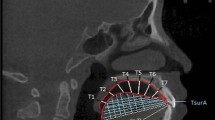

In order to reconstruct 3D palatal morphology and compare it among different groups, CBCT images were reoriented by the identical 3D reference plane and exported as digital imaging and communications in medicine (DICOM) format by Dolphin software. The plane tangent to the most inferior slice of maxillary alveolar bone was defined as the horizontal plane. The plane passing through the ANS-PNS line and perpendicular to the horizontal plane was defined as the sagittal plane. The plane perpendicular to the above two planes was defined as the coronal plane [13, 14] (Fig. 1).

Reorientation for the reconstruction of the three-dimensional (3D) palatal morphology. Horizontal plane, the plane tangent to the most inferior slice of the maxillary alveolar bone; sagittal plane, the plane passing through the ANS-PNS line and perpendicular to the horizontal plane; coronal plane, the plane perpendicular to the above two planes